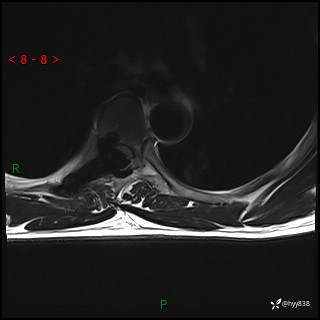

axi T2WI